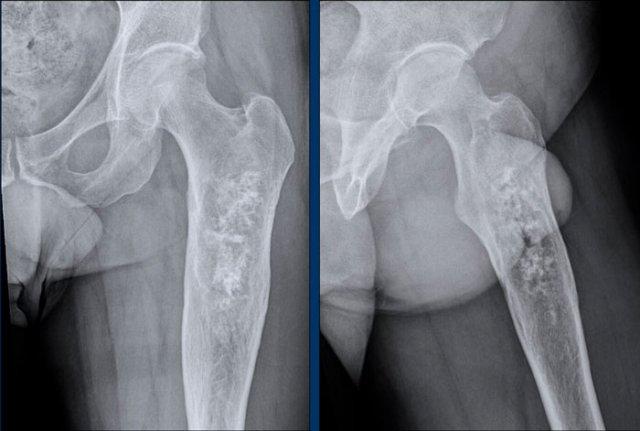

Hình ảnh

Có một tổn thương tiêu xương được xác định rõ >10 cm ở thân xương đùi đoạn gần với vôi hóa chất nền sụn dạng bỏng ngô.

Có sự giãn nở của xương, tuy nhiên không có dấu hiệu xói mòn vỏ xương rõ ràng hay phản ứng màng xương.

Kết luận

Dựa trên hình ảnh X-quang đơn thuần, khối u này có thể là một ACT hoặc sarcoma sụn độ cao hơn. Bước tiếp theo là thực hiện MRI để đánh giá đặc điểm chi tiết hơn.